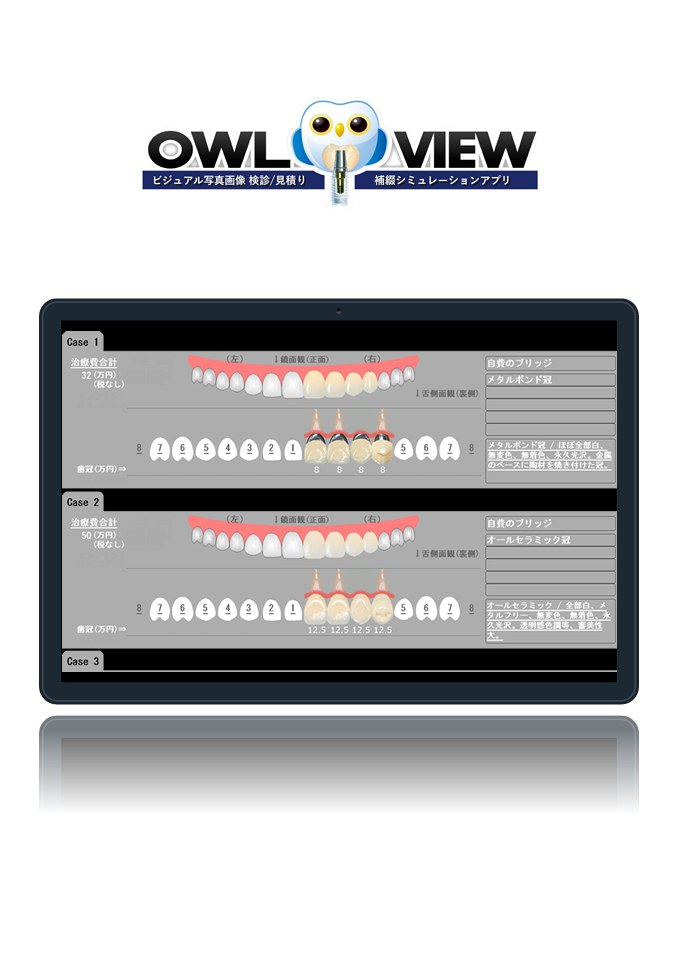

見積もり書も簡単

個別設計での写真画像見積もり書が簡単に作成できます!

補綴説明シミュレーションも簡単

ビジュアルな写真画像での補綴説明シミュレーションが簡単にできます!

補綴説明

これはサンプルの説明文です。各箇所に短めの説明文を入れます。これはサンプルの説明文です。各箇所に短めの説明文を入れます。

見積/入金

これはサンプルの説明文です。各箇所に短めの説明文を入れます。これはサンプルの説明文です。各箇所に短めの説明文を入れます。